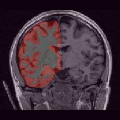

To compare the proposed approach to the mSENSE333SENSE reconstruction implemented by the Siemens scanner, software ICE, VB 17. one, Fig. 1 illustrates coronal anatomical slices reconstructed with both algorithms while turning off the temporal regularization in 4D-UWR-SENSE, so resulting in the so-called 3D-UWR-SENSE approach. Red circles clearly show reconstruction artifacts and noise in the mSENSE reconstruction, which have been removed using our 3D-UWR-SENSE approach. Comparison may also be made through reconstructed slices for and , as well as with the conventional acquisition (). This figure shows that increasing generates more noise and artifacts in mSENSE results whereas the impact on our results is attenuated. Artifacts are smoothed by using the continuity of spatial information across contiguous slices in the wavelet space. Depending on the used wavelet basis and the number of vanishing moments, more or less (4 or 8 for instance) adjacent slices are involved in the reconstruction of a given slice. For instance, using Symmlet filters of length 8 (4 vanishing moments) as in the conducted experiments here, 8 adjacent slices are involved in reconstructing a given slice. However, it is worth noticing that the introduced smoothing is anisotropic, in contrast to standard Gaussian smoothing that could be applied to anatomical data. Fig. 1 also compares 3D-UWR-SENSE and mSENSE reconstructed slices when applying additional spatial smoothing to the later with a mm3 Gaussian kernel. Comparisons clearly show that, even at such low spatial smoothing level, mSENSE images suffer from a significant blur. Moreover, the artifact present at for mSENSE (left red circle) is spread out but not fully removed by applying isotropic spatial smoothing.

In order to evaluate the impact of such smoothing, classification tests have been conducted based on images reconstructed with both methods. Gray and white matter classification results using the Morphologist 2012 pipeline of -MRI toolbox of Brainvisa software444http://brainvisa.info at and are compared to those obtained without acceleration (i.e. at ), considered as the ground truth. Displayed results in Fig. 2 show that classification errors occur due to reconstruction artifacts for mSENSE, especially at . Results show that the gray matter is better classified using our 3D-UWR-SENSE algorithm especially next to the artifact into the red circle (Fig. 2 []), which lies at the frontier between the white and gray matters. Moreover, reconstruction noise with mSENSE in the centre of the white matter (left red circle in Fig 2 []) also causes miss-classification errors far from the gray/while matter frontier. However, at and classification performance is rather similar for both methods, which confirms the ability of the proposed method to attenuate reconstruction artifacts while keeping classification results unbiased.